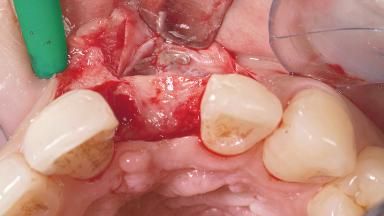

A 30-year-old female patient had lost tooth 21 and was referred to our clinic for consultation and treatment. Due to advanced apical infection, tooth 21 had been extracted two months earlier at another clinic and an acrylic-resin tooth had been bonded to the adjacent teeth. The patient desired implant treatment to avoid any damage to the adjacent natural teeth. While the patient had no history of any systemic disorder, she was a heavy smoker and exhibited medium to advanced periodontitis in the entire jaw. After the initial treatment to achieve a pocket probing depth of less than 4 mm and no bleeding on probing, a decrease in the height of the papillae mesial and distal to the extraction site and overall gingival recession were observed.

| Bone Augmentation | Horizontal|Staged |

| Augmentation Materials | Autogenous chips|Membrane |